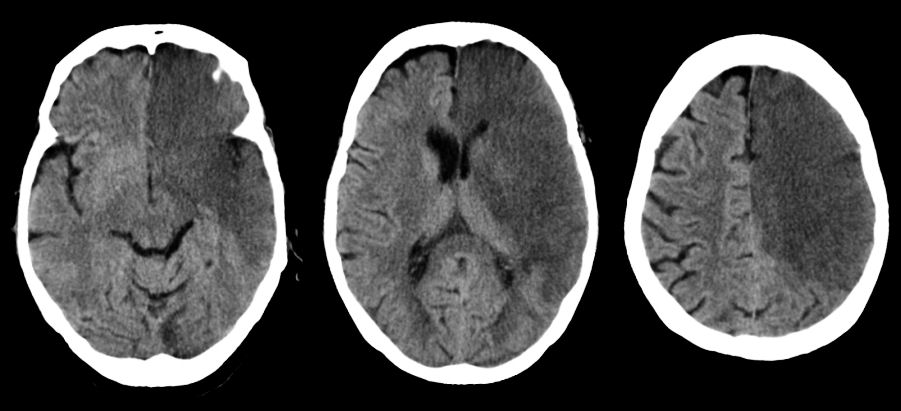

Хроническая ишемия головного мозга и лейкоареоз: симптомы и лечение